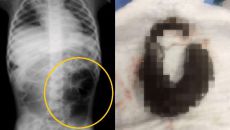

"이게 나왔다고?"..6세 여아 뱃속에서 나온 거대한 덩어리, 뜻밖의 정체 [헬스톡]

[파이낸셜뉴스] 복통을 호소하던 6세 여아의 뱃속에서 머리카락 덩어리가 발견된 사례가 보고됐다. 22일 큐레우스 저널에 따르면- 7시간전